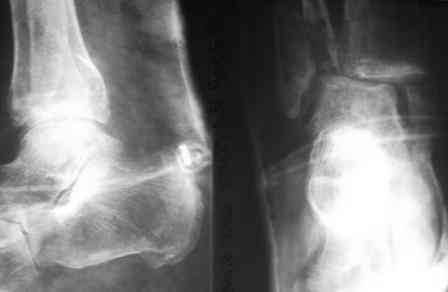

Анамнез: в 1992 г. оперирован в РНЦ «ВТО» по поводу ложного сустава шейки правого бедра (Р-снимок в приложении), 1994 перенес инсульт с исходом в правосторонний гемипарез. Передвигался без костылей, имея укорочение этой конечности на 3,5 см, порочную сгибательно-приводящую установку правого бедра и ДОА правого коленного сустава III ст. с перегрузкой латерального компартмента. Имеются дегенеративно-дистрофические изменения в поясничном отделе позвоночника. Больной до последнего времени «таксовал» на своей машине. 23 дня назад, поскользнувшись, упал в своей квартире, получил 2-х лодыжечном переломе костей правой голени с подвывихом стопы кнаружи (Р-граммы правового коленного и г/стопного суставов прилагаются). Помощь оказана в городском травмпункте г.Темиртау (Казахстан) Лечился гипсовой шиной, как рассказывает больной манипуляций на г/стопном суставе не проводили, посчитали, что все в порядке. Мое мнение - для создания опорной конечности необходимо произвести первичный артродез.Попов Виктор, г.Караганда.

Трудно согласиться с мнением о первичном артродезе, срок-то небольшой, двухлодыжечний перелом: пластина на наружную лодыжку, а внутренную шурупами.

Зачем же замыкать,если можно слепить?Я думаю,что лучше это сделать открыто.Главное,восстановить длину наружной лодыжки,ну и репонировать внутреннюю.И обязательно R-контроль на столе(а то я однажды оставил подвывих:( , потом было очень стыдно!!!)